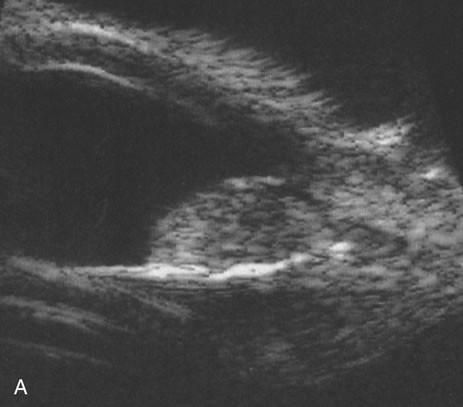

Necrotic melanomas account for approximately 5% of uveal melanomas; in the majority of cases, there is intraocular inflammation accompanying the cataract.7–9Figures 1 and 2 demonstrate a typical case. The patient had a long history of unilateral decreased vision. The eye had become painful 1 month before admission, and he was referred for evaluation of uveitis. Clinically, there was a dense, unilateral cataract with significant intraocular inflammation, which was manifested as a ciliary flush with 2+ cells and flare. Media opacity obscured all fundus detail. An immersion B-scan demonstrated a large intraocular tumor that was most consistent with a uveal melanoma. The eye was removed, and the diagnosis was confirmed histologically.10

Unfortunately, imaging studies are not always diagnostic. The A- and B-scans shown in Figures 3 and 4 were from a patient with unilateral media opacity referred for evaluation and treatment of a presumed uveal melanoma. Occasionally, if the cataractous lens is scanned tangentially, artifact can occur. A repeat ultrasound at our institution was negative for tumor, and the referral ophthalmologist who performed a cataract extraction noted that no tumor was present and that the patient has an excellent visual outcome. In contrast, the patient shown in Figure 5 was referred with a presumed uveal melanoma with secondary inflammation and a history similar to that described for the patient shown in Figure 111 Ultrasound and CT examinations were not diagnostic. Because the eye was blind and painful, it was enucleated, and an extremely necrotic uveal melanoma was noted histologically. In some necrotic melanomas, the fundus cannot be visualized and the diagnosis cannot be established with imaging studies. Very rarely, a necrotic uveal melanoma can produce sufficient pigment dispersion into the vitreous to obscure the correct diagnosis.12